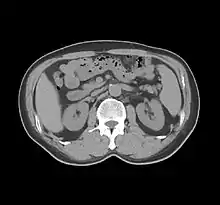

One frame of a modern CT scan of the abdomen.